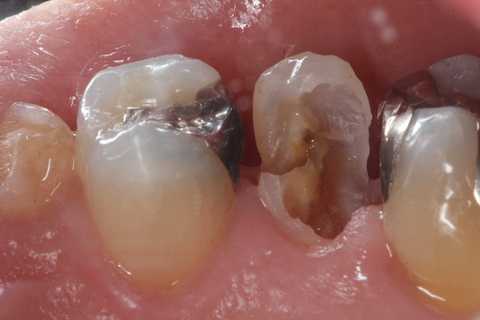

今日の充填治療55(遠心隣接面カリエス) 2023.12.21